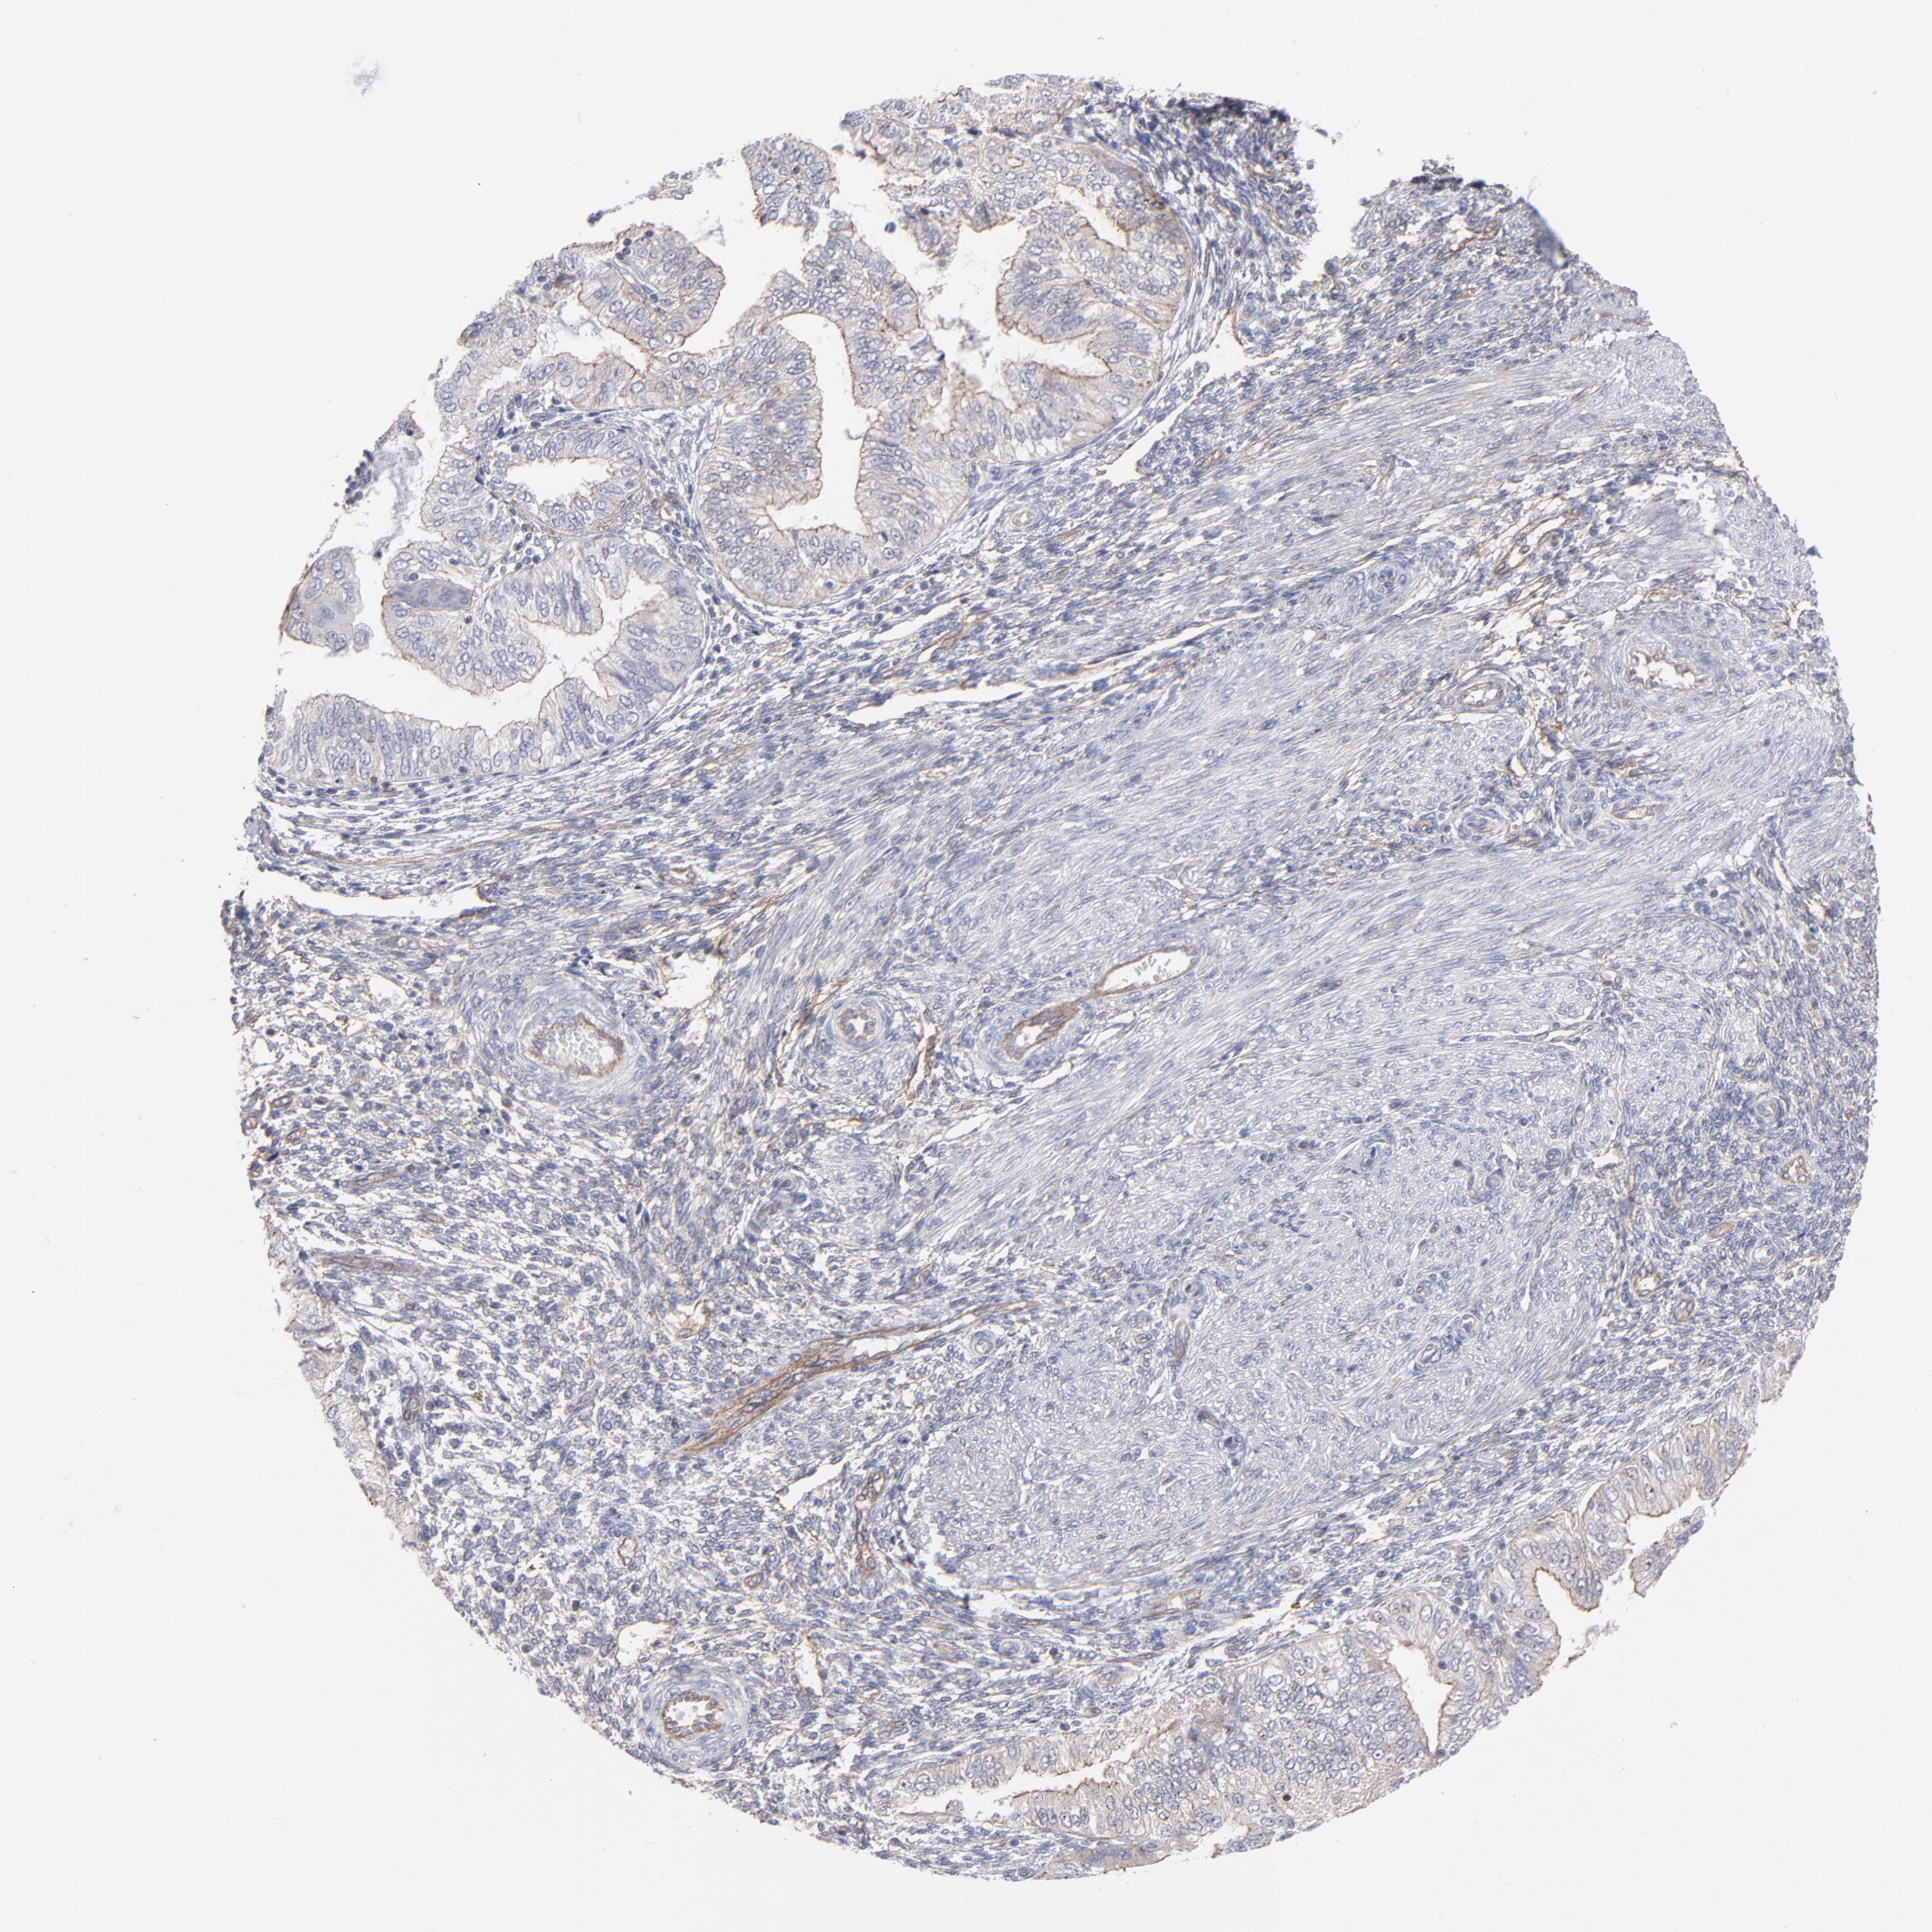

ENDOMETRIAL CANCER - Protein expressioni

A mouse-over function shows sample information and annotation data. Click on an image to view it in a full screen mode. Samples can be filtered based on level of antibody staining by selecting one or several of the following categories: high, medium, low and not detected. The assay and annotation is described here.

Note that samples used for immunohistochemistry by the Human Protein Atlas do not correspond to samples in the TCGA dataset.

Antibody stainingi

Antibody staining in the annotated cell types in the current human tissue is reported as not detected, low, medium, or high, based on conventional immunohistochemistry profiling in selected tissues. This score is based on the combination of the staining intensity and fraction of stained cells.

Each image is clickable and will lead to virtual microscopy that enables deeper exploration of all samples and also displays staining intensity scores, fraction scores and subcellular localization as well as patient and tissue information for each sample.

Antibody CAB003841

Staining

High

Medium

Low

Not detected

Intensity

Strong

Moderate

Weak

Negative

Quantity

>75%

75%-25%

<25%

None

Location

Nuclear

Cytoplasmic/membranous

Cytoplasmic/membranous,nuclear

Adenocarcinoma, NOS